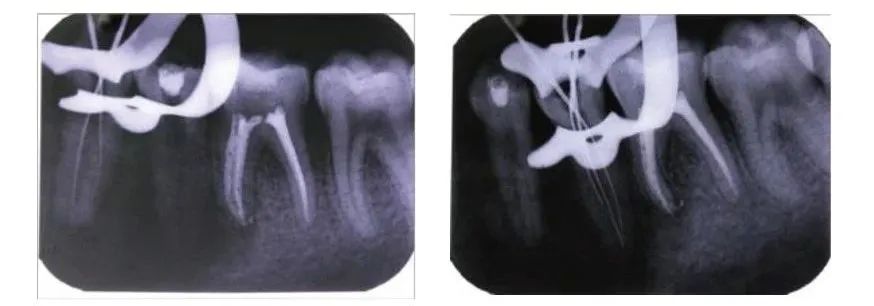

Post-curettage, pre-treatment CBCT for teeth 34 and 35 (2014.8.12)

Pulp opening, using sharp files under a microscope to prepare the root canal, tooth 34 has two canals, tooth 35 has three canals (2014.8.12)